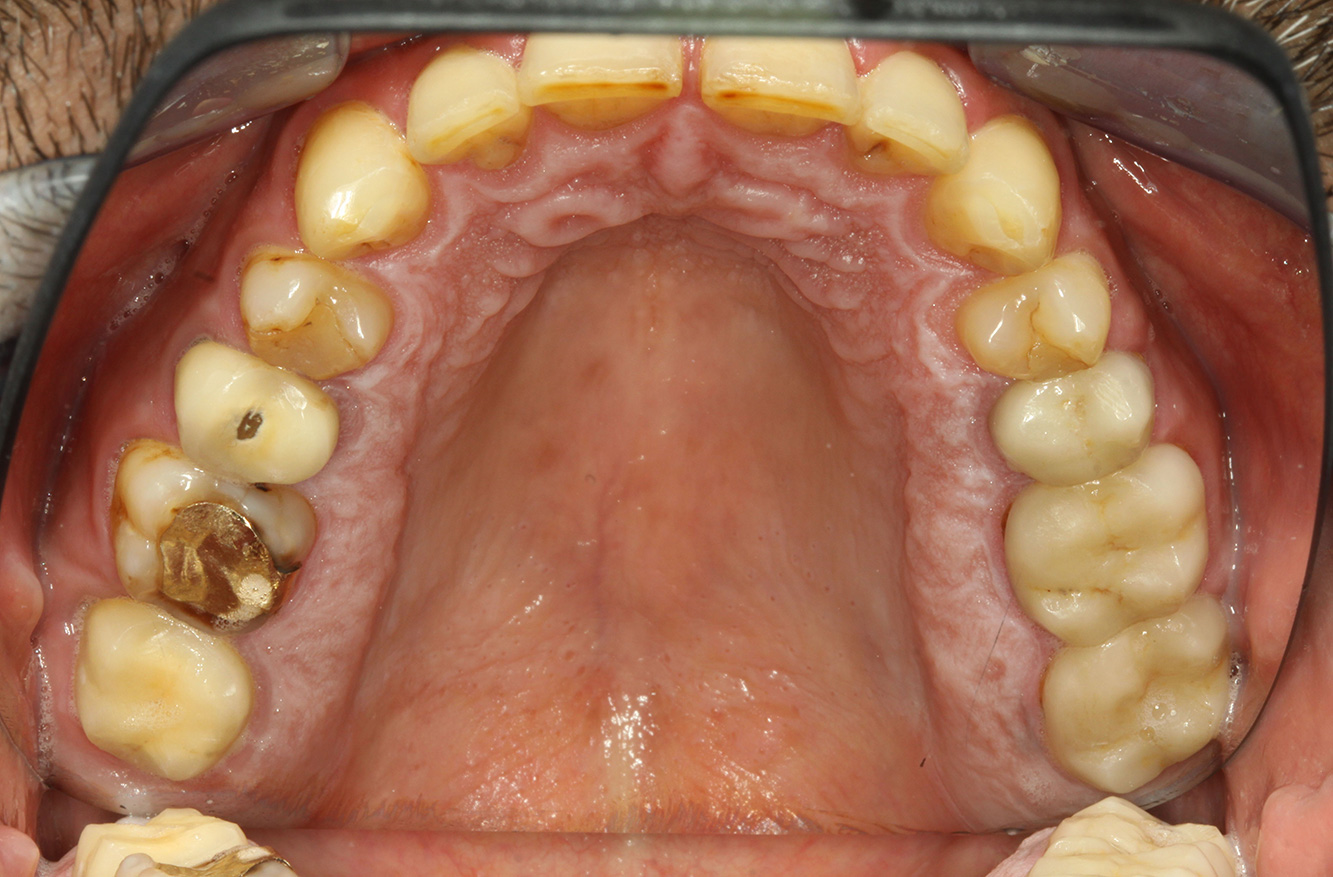

Der Endokarditis-Patient mit aktiven Kariesläsionen*

Der Patient ist 39 Jahre mit Z.n. Herzklappenersatz wegen Klappenfehlers und Endokarditis. Als Antikoagulans (Gerinnungshemmer) wird regelmäßig ASS 100 eingenommen. Aus dem Bereich Lebensstil ist die Ernährungsweise als kariesfördernd einzustufen, da mit hoher Regelmäßigkeit zuckerhaltige Lebensmittel sowie sechs bis sieben Mahlzeiten täglich verzehrt werden. Die Mundgesundheit des Patienten zeigt ein mittleres Kariesrisiko mit aktiven Läsionen. Das Parodontitisrisiko ist niedrig, es besteht eine Gingivitis. Es ergeben sich folgende Empfehlungen für die Prophylaxebehandlung.